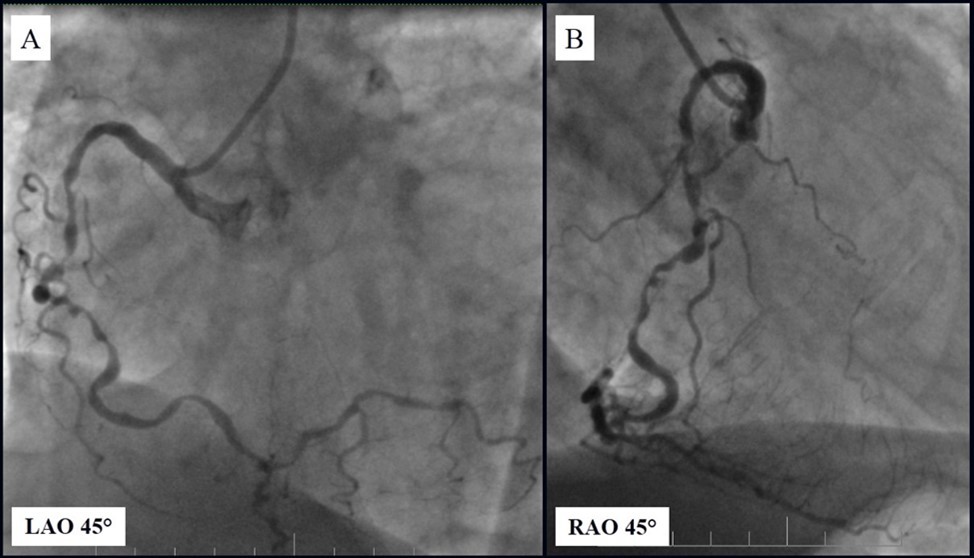

Angiography revealed rare anatomical variation LMCA quadrifurcation (Figure 1, Figure 2), 50% stenosis of the distal part of the LMCA, 40% stenosis of the ostial segment of left anterior descending (LAD) artery and diffuse prolonged 70-75-95% stenosis in mid-segment (Figure 3), 75% stenosis of the ostial segment of the circumflex (CX) artery, 75% stenosis of the ostial segment of the first marginal branch (OM1), 75-90% stenosis of the proximal segment of the intermediate artery (IMA), prolonged diffuse severe 90-95% stenosis of mid-segment of the right coronary artery (RCA) (Figure 4).

Figure 3.Prolonged diffuse severe 90-95% stenosis of mid-segment of the right coronary artery. A - Left anterior oblique 45° projection; B – Right anterior oblique 45° projection.